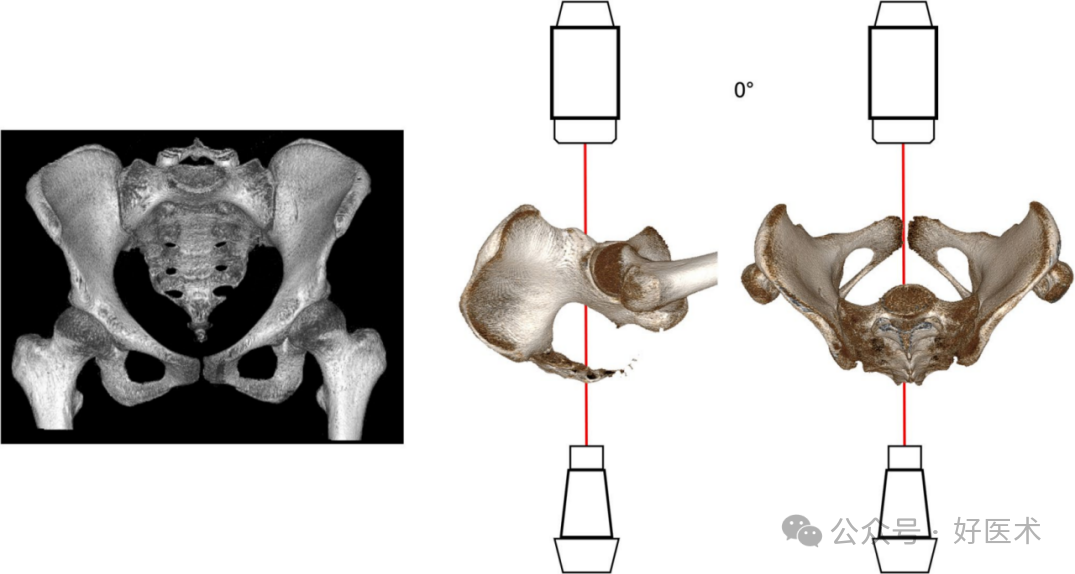

骨盆前后视图 (PAP)

在**骨盆正位片上,双髋应从髋关节处内旋15–25°(在两侧大转子的侧面可视化中,以及小转子部分重叠的情况下)。骶骨的中线应穿过耻骨联合的中心(图3)。获得**影像的放射学标准包括:骨盆整体在图像内,闭孔、髋臼泪滴和髂翼的对称显示。骶尾关节的理想投影应位于上支上缘上方1–3厘米处。必须考虑骨折情况。

图 3 显示透视机定位的骨盆三维图。